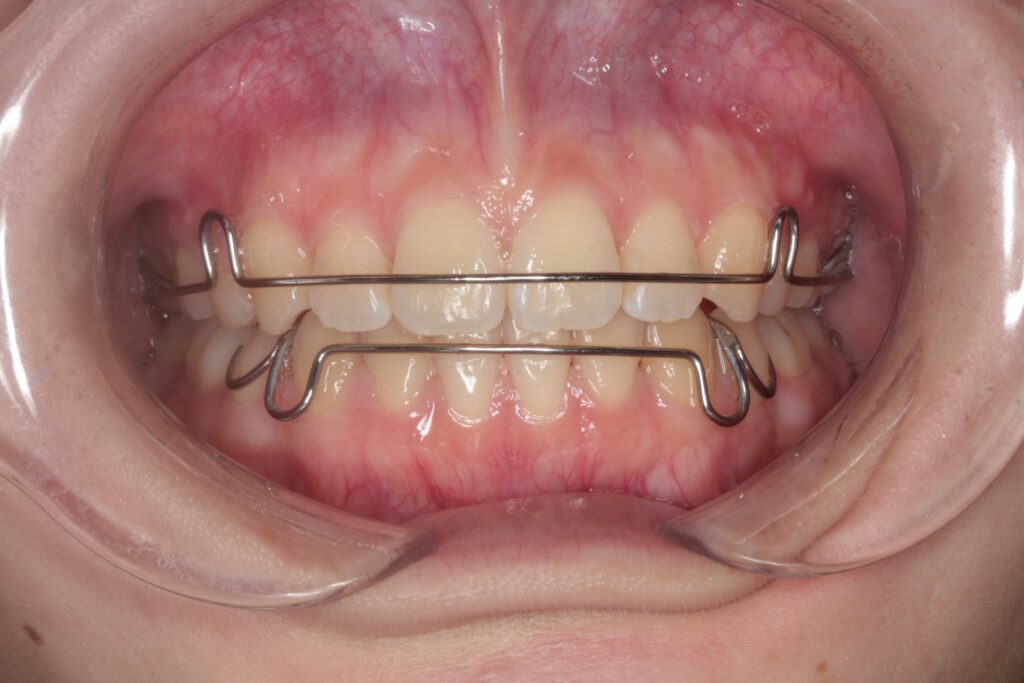

治療の評価と保定

矯正治療が終わったあと、きれいに整えた歯並びを維持するためには「保定(ほてい)」が欠かせません。治療が完了しても、歯は時間とともに元の位置に戻ろうとするため、治療後の管理が非常に重要になります。

保定の重要性

矯正装置を外したあと、整えた歯並びを安定させるために「保定装置(リテーナー)」を使用します。治療後すぐの時期は歯が動きやすく、保定の協力が結果に大きく影響します。